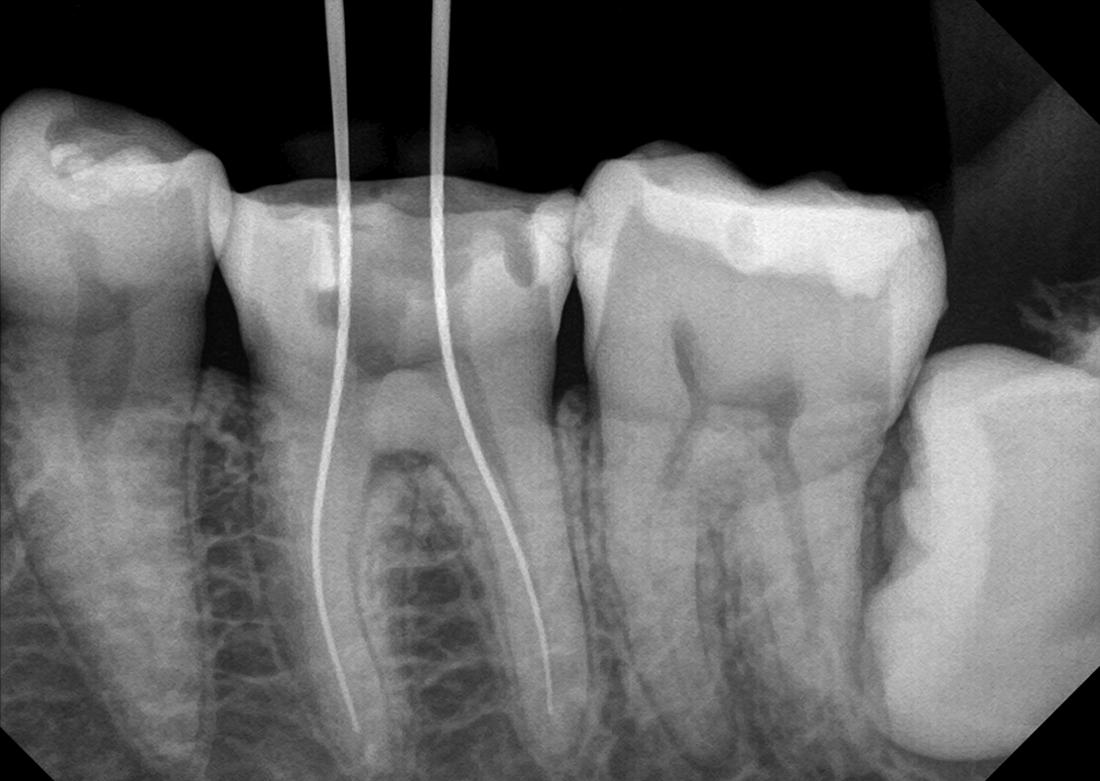

KLİNİK FOTOĞRAFLAR

Firmanın uzun yıllara dayanan dental görüntüleme tecrübesi ile son teknoloji sensor reseptörleri kullanılarak üretilmiştir ve görüntü kalitesi mükemmel düzeydedir.